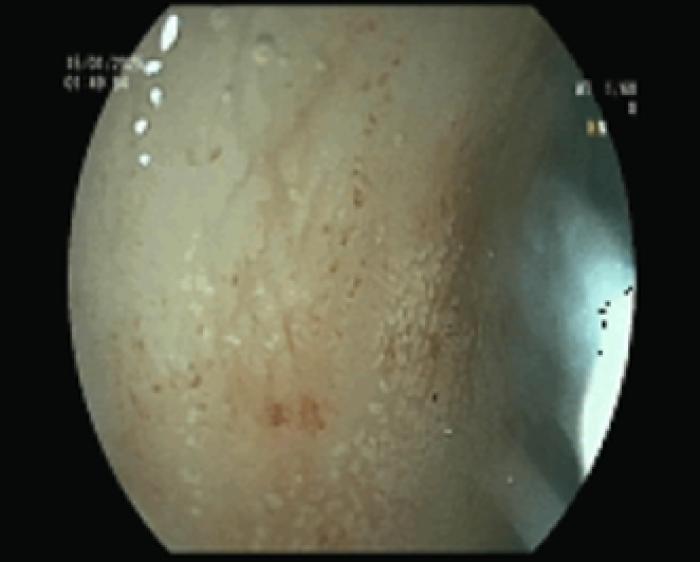

- Atrofia severa de vellosidades duodenales (Figura 4)

- Gastritis congestiva ligera (Figura 12)